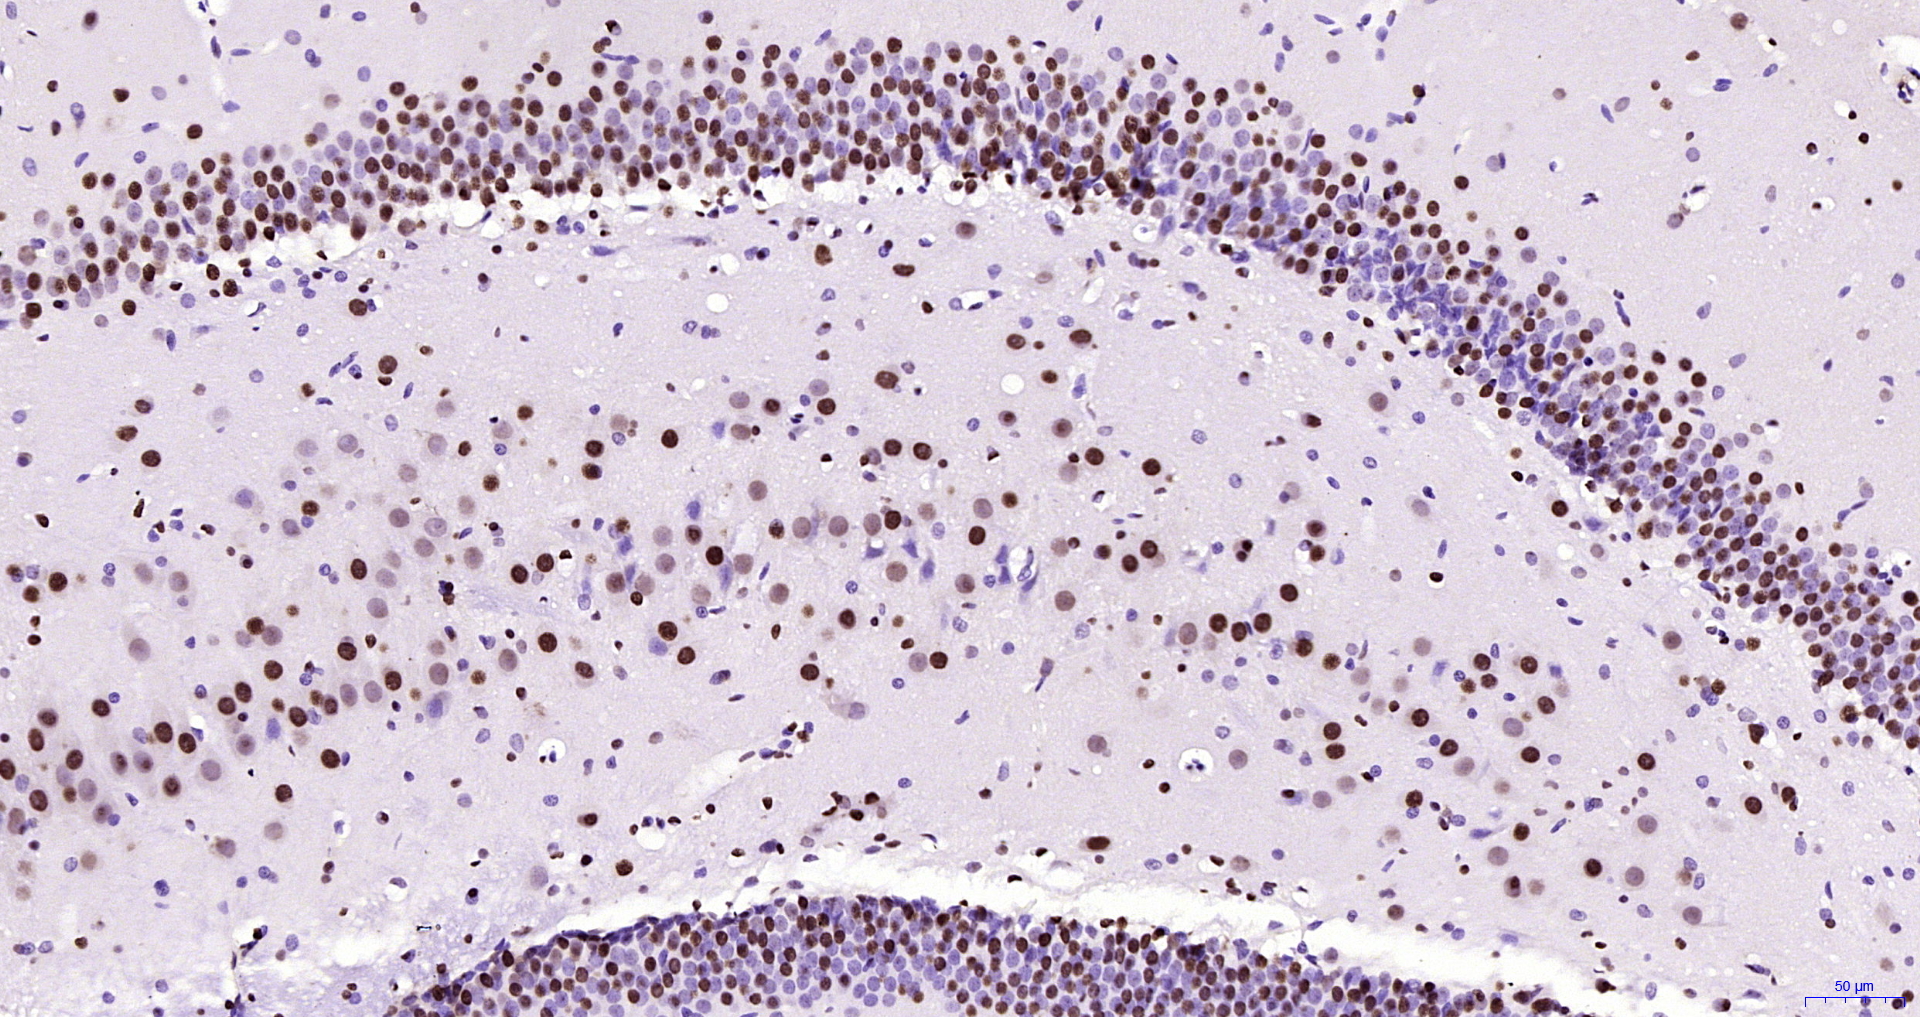

DAB,即3,3’-二氨基联苯胺(3,3’-diaminobenzidine)是辣根过氧化物酶(Peroxidase)的常用生色底物,在过氧化氢的存在下失去电子而呈现出颜色变化,形成浅棕色不溶性产物。用于检测过氧化物酶的活性,它灵敏度高,特异性好,是HRP结合物最常用的底物,常在免疫组化,原位杂交,Western blot等膜显色或检测细胞或组织内源性的过氧化物酶中应用广泛。

DAB (3,3′-Diaminobenzidine; 3,3′,4,4′-Biphenyltetramine; 3,3′,4,4′-Tetraaminobiphenyl) is Peroxidase substrate suitable for use in immunoblotting and immunohistological staining procedures. This substrate produces an insoluble end product that is brown in color and can be observed visually. The kit contains three components: the DAB Chromogen, Substrate Buffer and Staining Assistant. All components are in liquid form. This new 3-Solution DAB product has improved stability, ease of formulation, and greater sensitivity than previous DAB products.